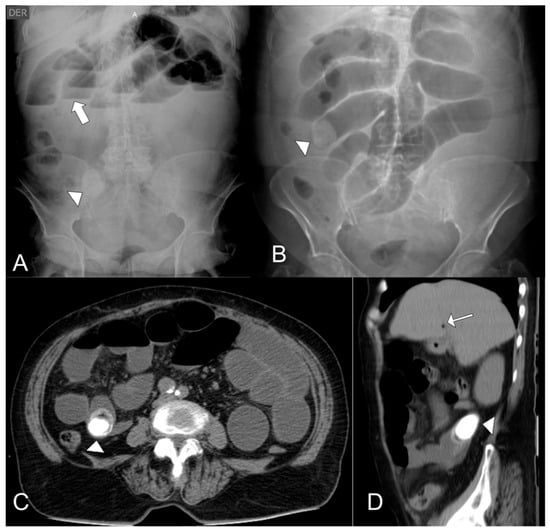

Managing Gallstone Ileus and Surgical Considerations in Resource-Limited Settings: A Case Series from the Amazon Jungle

by Santiago Andrés Suárez-Gómez, Valentina Velasco-Muñoz, Nicolás Escobar, Fernando Escobar Castañeda and Oscar Guevara

Complications 2026, 3(1), 2; https://doi.org/10.3390/complications3010002 - 9 Jan 2026

Gallstone ileus is a rare but serious complication of gallstone disease, often requiring surgical intervention. While enterolithotomy remains the standard treatment, the role of additional biliary surgery, particularly subtotal cholecystectomy, remains controversial. This study examines the management of gallstone ileus in a rural [...] Read more.

Gallstone ileus is a rare but serious complication of gallstone disease, often requiring surgical intervention. While enterolithotomy remains the standard treatment, the role of additional biliary surgery, particularly subtotal cholecystectomy, remains controversial. This study examines the management of gallstone ileus in a rural setting, where limited surgical resources and access to specialized biliary interventions pose unique challenges. We present a case series of four patients diagnosed with gallstone ileus in a rural healthcare facility. All patients underwent initial enterolithotomy for bowel obstruction relief. Surgical outcomes, complications, and the necessity for a second intervention, including subtotal cholecystectomy, were evaluated. Ever patient had a successful recovery. Of the four cases, two patients underwent a subtotal cholecystectomy. No perioperative mortality was observed, but limited access to advanced imaging and specialized biliary surgery influenced clinical decision-making. The rural setting in which these series occurred comes with its unique challenges regarding resource management and technological demands. Full article

Show Figures

Figure 1